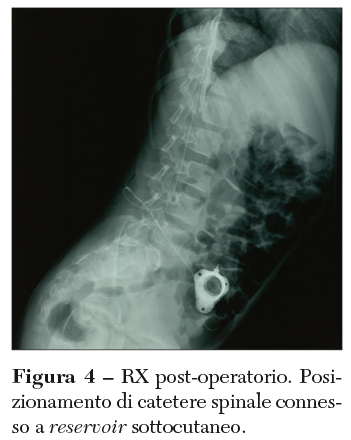

Il Baclofen è un farmaco nato come molecola antiepilettica ma dotato di una forte capacità di controllo sulla spasticità muscolare. In particolare, la capacità di ridurre il tono muscolare dipenderebbe dalla capacità di legarsi ai recettori GABAB nel midollo spinale, con conseguente riduzione dell’effetto eccitatorio sui motoneuroni delle corna anteriori del midollo spinale. Per essere efficace, il farmaco deve entrare nel liquor cefalorachidiano (LCR) e ciò rende necessario, nella somministrazione per os, l’impiego di posologie dell’ordine di mille unità superiori a quelle efficaci per riuscire ad avere una concentrazione liquorale adeguata. Il rischio di effetti indesiderati va quindi inevitabilmente ad aumentare e può consistere in sedazione, cambiamenti del comportamento, confusione, atassia, poliuria, insonnia. Al contrario, la somministrazione del Baclofen direttamente nello spazio liquorale spinale subaracnoideo, ossia nella sede di azione del farmaco, permette di somministrarne dosi nell’ordine di microgrammi e di ridurre quindi i rischi di effetti collaterali. Per una selezione accurata dei pazienti con maggiori possibilità di beneficiare del Baclofen IT, è possibile eseguire una procedura test prima dell’intervento. Il grado di spasticità viene valutato prima e dopo la somministrazione del farmaco per via IT. Tale test può essere effettuato o tramite puntura lombare o mediante impianto chirurgico del catetere spinale collegato poi a un piccolo reservoir posizionato sottocute in cui può essere iniettato il Baclofen (Figura 4).